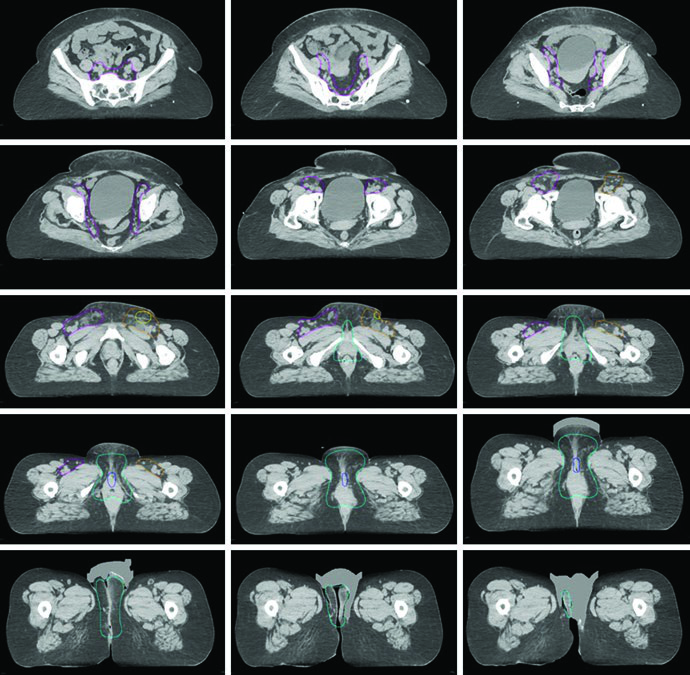

As figuras do capítulo ajudam a traduzir essas regras em decisões concretas. Na radioterapia definitiva da Fig. 23.1, a paciente tinha estádio FIGO IIIB, doença confinada à vulva considerada irressecável pela proximidade com meato uretral e vagina e dois linfonodos inguinais direitos avidamente captantes no PET. O GTV primário foi contornado em azul; o CTV1, em ciano, cobria toda a vulva com exclusão de osso e músculo adjacentes; o CTV2, em magenta, abrangia linfonodos pélvicos e inguinofemorais. Já a Fig. 23.2 mostra o cenário pós-operatório em uma paciente com estádio FIGO IIIA, margem patológica de 7 mm e um linfonodo inguinal esquerdo não sentinela de 3 cm comprometido sem extensão extranodal. Nessa situação, pelve e região inguinofemoral direita receberam 45 Gy, a vulva 50 Gy e a região inguinofemoral esquerda 55 Gy, tudo em 25 frações, com expansões de 5 mm por causa do CBCT diário.

A Fig. 23.3 acrescenta um ponto que costuma passar despercebido: mesmo entre especialistas em IMRT há variabilidade relevante no contorno. O consenso aparece em amarelo, o consenso modificado em vermelho e os contornos individuais de 14 médicos aparecem sobrepostos em dois casos, um localmente avançado e outro pós-operatório. O consenso modificado foi retraído do espaço entre vulva e virilha e também da superfície cutânea quando essas áreas foram consideradas de baixo risco. Em outras palavras, reduzir volume é possível, mas apenas quando o raciocínio de risco é explícito.